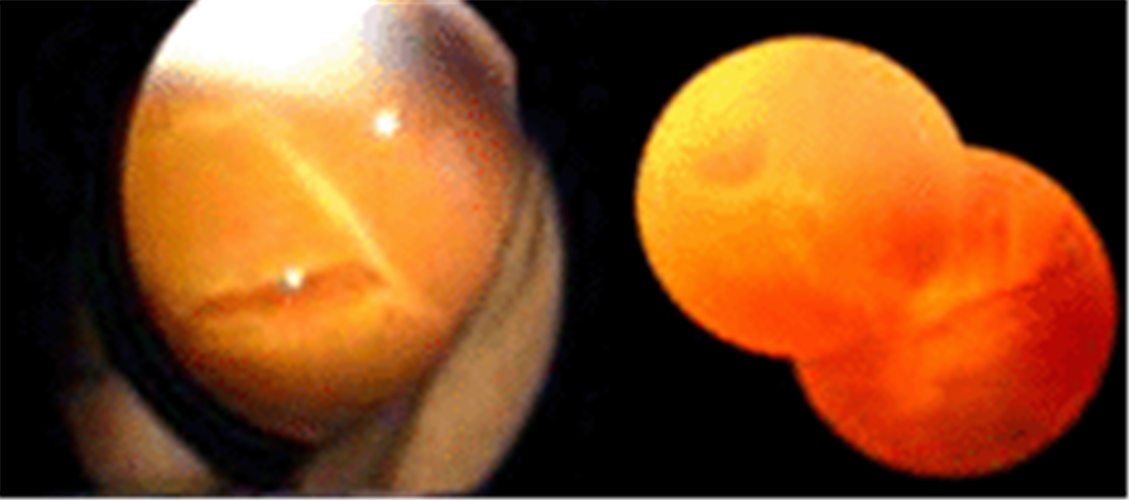

雙眼孔源性視網膜脫落